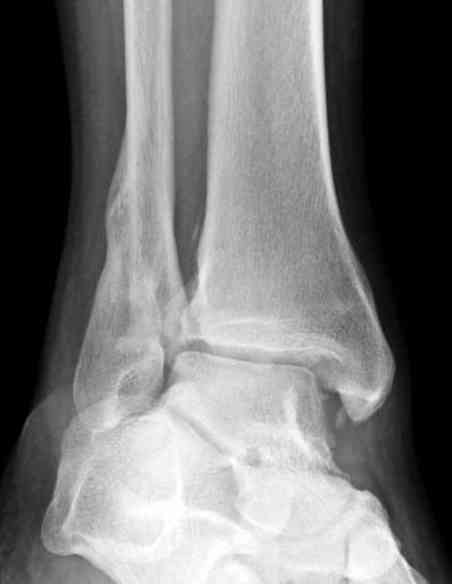

Мне кажется есть все основания попытаться сделать остеосинтез. Боль вследствие нестабильности. Нестабильность вследствие неанатомичного положения дистального отломка малоберцовой кости. Через 1,5 вполне возможно разобщить, репонировать и фиксировать длинный косой перелом наружной лодыжки. Вероятно, одновременно придется делать медиальный доступ для мобилизации внутренней лодыжки. Мы оперируем таких пациентов, функциональные (объем движений) результаты конечно хуже по сравнению с теми кого оперируем в первые 5-10 дней, но вполне удовлетворительные.

Согласен, на предоставленных рентгенограммах все основания для проведения открытого остеосинтеза.

сроки действительно небольшие, но если мы его и возьмем, то пройдет еще минимум неделя, кроме того смущает впечатление сращения н/лодыжки, похоже, что придется не разобщать,а остеотомировать, формирование оссификатов в полости сустава с медиальной стороны, да и сам пациент 1,5 месяца по поводу своей травмы сильно не напрягался